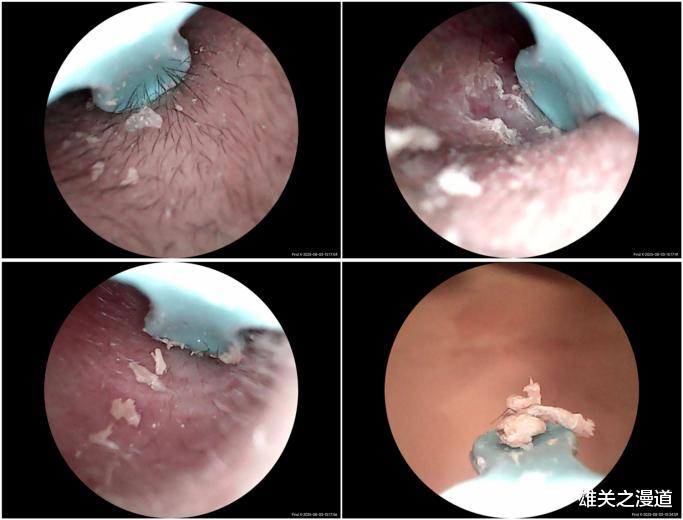

耳勺端的摄像头是这款西圣Find X智能可视耳勺的核心部件,也是实现智能可视化的关键。这款摄像头搭载旗舰级影像系统,1500万高清像素精准捕捉耳道每一处细节,解析力达微米级别,画质媲美专业内窥镜。融合F2.0大光圈与多层光学镀膜镜组,不仅成像清晰锐利,更真实还原耳道色彩与纹理,让每一次清洁都更精准、更安全、更安心。自研升级的A-Zoom 2.0技术,实现实时毫秒级自动对焦,操作过程中即使旋转、推进、微调视角,画面依然不跑焦、不模糊,真正做到视线动,清晰不动,真正做到清晰跟随视野,每一帧都“眼见为实”。

这款智能可视耳勺还配置了三轴智能陀螺仪和无人机专用双频Wi-Fi芯片,没看错,耳勺都配上三轴智能陀螺仪和无人机专用双频Wi-Fi芯片,太卷了!同时西圣为这款耳勺开发了配套的可视耳勺APP,千万像素摄像头+三轴智能陀螺仪+APP,三者结合,耳朵内部的情况清晰、稳定的展现,一览无遗,何止耳垢,就是耳道绒毛都一清二楚,加上WIFI芯片最高30FPS传输速率,彻底告别画面的卡顿,能轻松查看并安全地清理耳道,避免造成不必要的伤害!同时在掏耳过程中,APP端可以对画面进行拍照、录像和缩放操作。